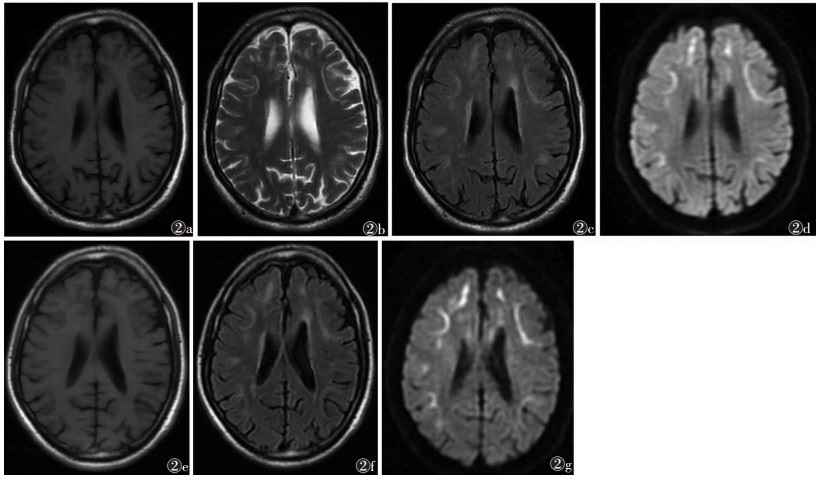

2 结果5例病灶位于双侧额叶、顶叶、枕叶,侧脑室周围脑白质及半卵圆中心,其中2例主要位于额叶(图 1),2例主要位于额叶、顶叶(图 2),1例主要累及额叶、顶叶、枕叶。病灶最大径4.9~23.1 mm,平均(14.3±3.2)mm。4例行CT平扫均呈低密度,部分病变密度欠均匀,边缘模糊(图 1a)。4例行MRI扫描,T1WI呈不均匀低信号(图 2a),T2WI、T2 FLAIR呈不均匀高信号(图 1b,2b,2c),T2 FLALR上病灶呈对称性不规则或卵圆形,DWI上皮髓质交界处呈U形高信号,病灶边缘模糊(图 1c,2d)。2例行MRI增强扫描示病灶内信号均匀,未见明显强化。

| 图 2 女,45岁,头晕、头痛3个月 图 2a T1WI示病灶呈低信号 图 2b T2WI示双侧额顶叶脑皮髓质交界处可见U形高信号 图 2c T2 FLAIR示病灶呈高信号 图 2d DWI可见病灶呈明显U形高信号 图 2~2g 分别为6个月后复查T1WI、T2 FLAIR、DWI图像,提示病变变化不明显 |

1例初诊后6个月行MRI平扫复查,病变变化不明显(图 2e~2g)。